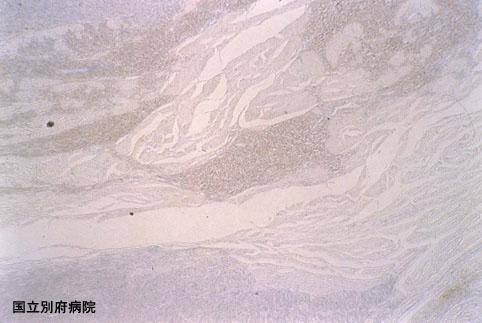

Criteria of Hist.ClassificationMalignant melanoma/

LocationLarge intestine(Colon)/Rectum

Macroscopic TypesType 1 Protuberant (polypoed) type/

Size40 -

Depth of Tumor Invasionsubserosa (subadventitia)